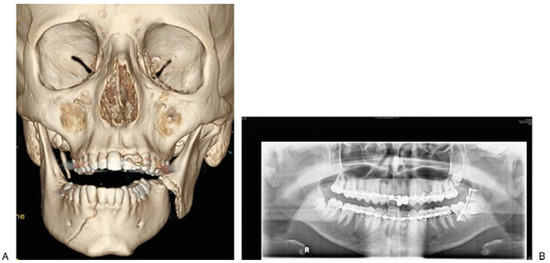

The classic Le Fort pattern of injuries are uncommon in children [14]. In the acute setting, accurate reduction of midfacial fractures can be challenging if the soft tissue is significantly disrupted or if there is significant bony comminution or bone loss. Midfacial fractures may be allowed to heal with a view to managing any subsequent problems secondarily. These problems may include malocclusion, tooth loss, and facial contour irregularities. Undergrowth of the maxilla is well described in patients who have had periosteal elevation in the process of repairing a cleft of the hard palate [38,39]. The periosteum provides the bone with a blood supply; it is osteoinductive and following elevation it can form a scar. Traumatic stripping of the periosteal tissues either from direct trauma or surgical repair may potentially cause growth disturbances. Malocclusion can be treated with orthodontics and orthognathic surgery as required. Permanent dentition loss may require osteointegrated implants, and contour issues may be addressed with onlay grafts or alloplasts (Figure 6).

Figure 6. (A) Midfacial and mandibular fracture following motor vehicle accident. (B,C) Subsequent midfacial hypoplasia and maxillary alveolar bone loss and class III relationship.